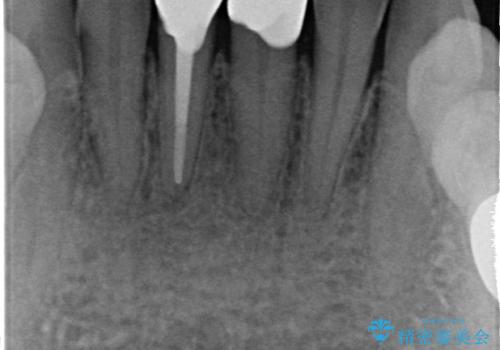

- 下顎前歯の見た目が気になるといらっしゃった方の症例です。

右下1の再根管治療終了後、オールセラミッククラウン(スペシャル)による補綴を行いました。